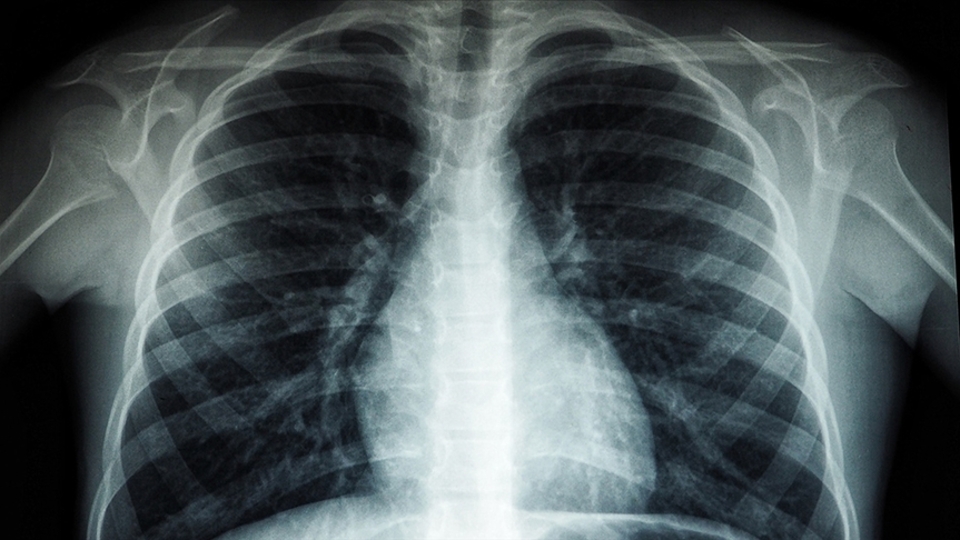

Hayatın hemen her alanında insanların maruz kaldığı plastiklerin vücut üzerindeki etkilerine her geçen gün bir yenisi ekleniyor. Son olarak İngiltere'de yapılan araştırma, yaşayan insanlardan alınan akciğer dokularında küçük plastik parçacıkları (mikroplastik) tespit edildiğini ortaya koydu.

Yemek yediğimiz plastik kaplardan tutun, kullandığımız arabada ve jelatinlerde de görebiliriz. Dolayısıyla günlük hayatımızda bu maddelere çok fazla maruz kalmaktayız. Hava kirliliğinin yoğun olduğu büyük şehirlerde de görülüyor. Zaten 20 yıl önce ortaya çıkan bazı çalışmalarda akciğer kanseri sebebiyle ameliyat olmuş hastaların akciğer dokularında bu mikroplastik adı verilen yabancı maddeleri görmüştük. Bu maddeler vücudumuza solunum yoluyla girdiğinde yaygın derecede reaksiyon yapmaktadır. Buna bağlı olarak akciğerde kansere kadar yol açabilen çeşitli hastalıklar görmekteyiz. Astım, akciğer hastalığı gibi hastaları tetiklediğini görüyoruz" şeklinde konuştu.

Yıldızeli, mikroplastiğin kansere de yol açtığını ifade ederek, "Özellikle meslek hastalıklarında bu durumu görüyoruz. Hastalarımızda, nefes darlığı, egzersiz kapasitelerinde düşme ve öksürük görülüyor. Bu çalışmayla birlikte meslek hastalığı olmayan bizim gibi normal insanlarda da plastik maddelerin akciğerimize geldiğini gördük. Normalde bir şeyi soluduğumuz vakit bunun akciğerlerimize kaçması ve aşağılara gitmesi mümkün. Ancak bizim daha aşağıda ufak dediğimiz damarsal düzeydeki yapılarımızda bile mikroplastikler görülebiliyor. Vücut bunu parçalayamadığı için bu kansere kadar yol açar. Mikroplastikler sigara içenler gibi riskli gruptakilerde kanser, astım gibi hastalıklara neden olur" diye konuştu.